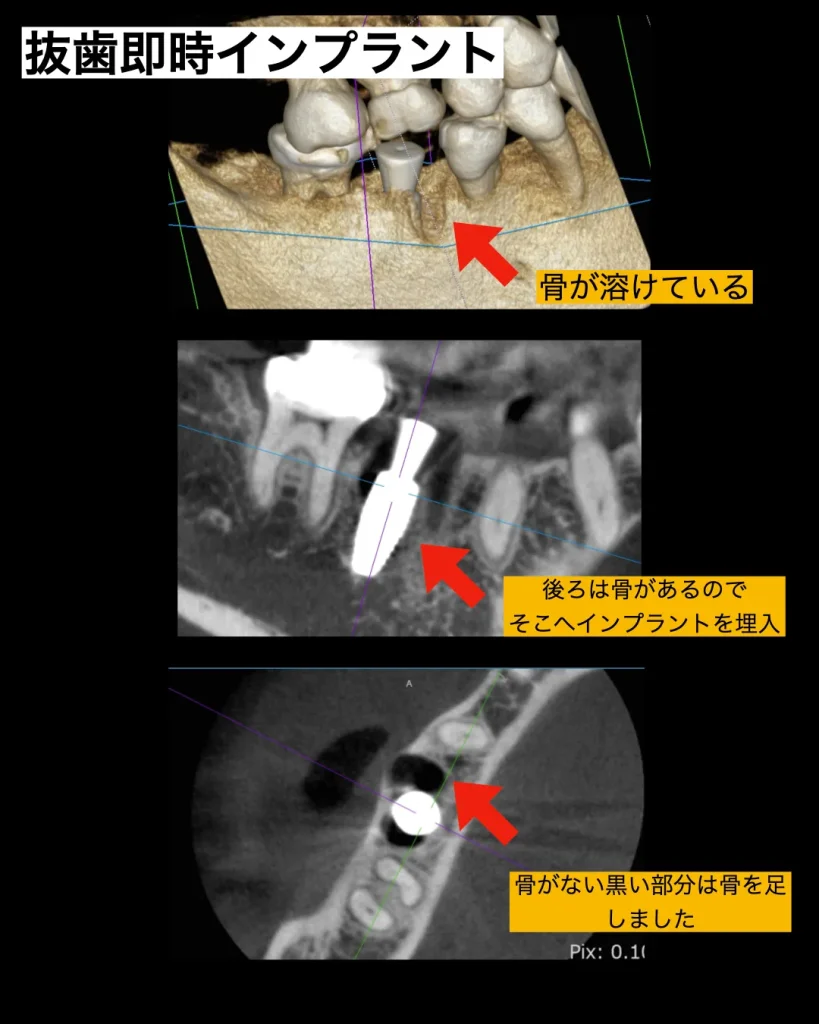

インプラント手術

当日は、まず、破折した歯を周りの歯肉を傷つけず繊細に抜歯を行いました。方法は中央で2つに分割して前根と後根に分け一つずつ抜歯することによって周りの骨の削除を減らし歯肉を傷つけることはしません。その後はインプラント窩をインプラント用ドリルにて形成しました。前方は歯牙の破折により、骨が溶けており膿があったのでしっかりと掻爬を行い、インプラントは後方の根の方に近くに埋入しました。抜歯したその日にインプラントを入れる事を抜歯即時インプラントと言います。今回のその抜歯即時インプラントで手術を行いました。

マイナーGBR

前の根は骨が溶けていたので、抜歯した後はマイナーGBRを行いました。

マイナーGBRとは、インプラントを埋入すると同時に行う小規模な骨造成のことを指します。本来GBRは一度歯茎を閉じて6〜8ヶ月ほど待ってからインプラント埋入することが多いですが、マイナーGBRはインプラント埋入と同時に骨を入れるので待ち時間がありません。その分、処置が難しくなり経験と技術が必要となります。